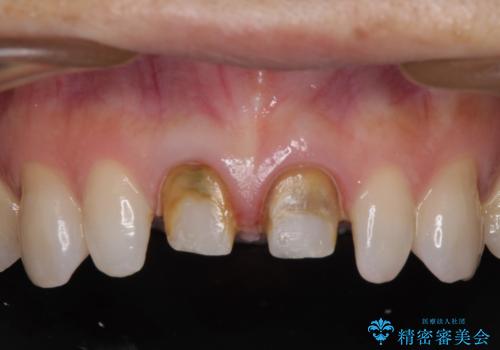

- 他院で奥歯に虫歯があると言われて、ご来院された患者様です。チェックしたところ、奥歯に虫歯は認められませんでした。

前歯に違和感や根尖病巣(根の先に細菌が溜まっている)が認められたため、治療をご提案しました。

セラミック治療と根管治療を行いました。

患者様は、もともと奥歯の虫歯を心配してご来院されましたが、前歯に問題が見つかりました。

金属を使用したメタルボンドクラウンが入っていたため、いつかオールセラミックにしたいときに根管治療も行ったほうが良いとご提案し、今回行いました。

歯と歯肉の境目の色は、歯自体が黒くなっている場合、完全にカバーすることは難しいです。